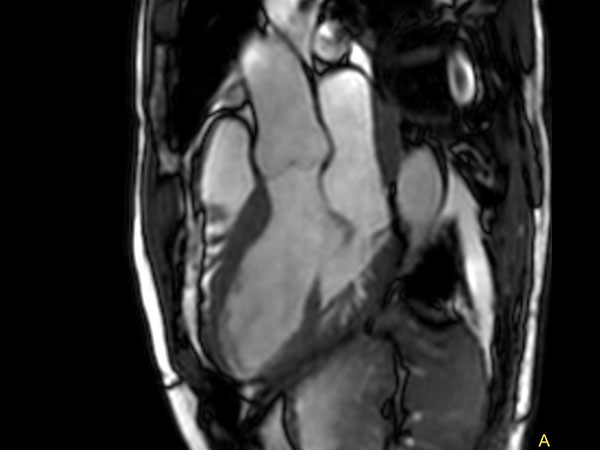

30 minute Cardiac Function and Fibrosis at 3.0T